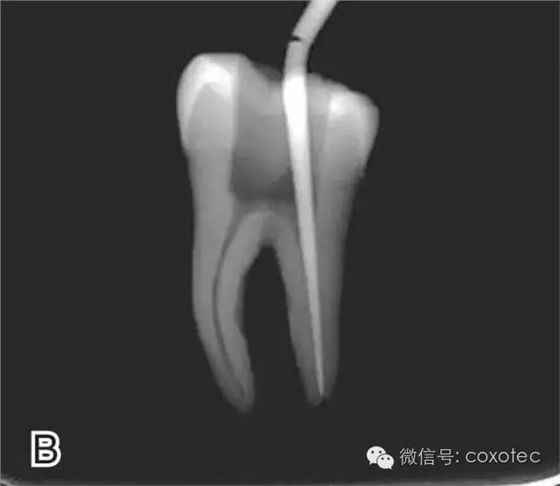

圖2 選擇垂直加壓器,A.試垂直加壓器 B.垂直加壓器在根內的位置 選擇非標準牙膠尖(如0.04、0.06 錐度牙膠尖)作為主尖,型號一般與根管預備最大號的器械型號一致,能到達距根尖0.5~1 mm 處,主尖尖段與根管壁緊密接觸。拍試尖X 線片進行確認(圖3)。

圖3 試尖,A.試主尖 B.拍試尖X片

將主尖的尖1/3 部分蘸一薄層根充糊劑,緩慢插入根管內,并左右旋轉主尖,以將根充糊劑均勻涂布于根管壁上,如圖4所示。

圖4 放置主尖及糊劑,A.放置主尖及糊劑 B.X線片下示主尖及糊劑的放置